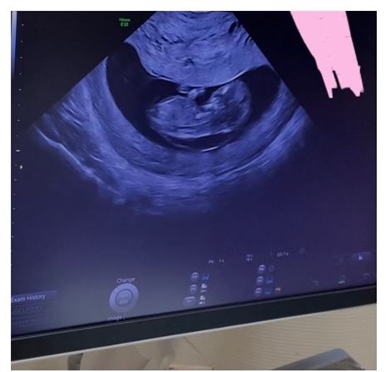

8月に第2子となる息子を出産していた光上さん。28日公開の動画では、妊娠9週目にたまたま診察してくれた超音波の名医から胎児のNT(※)の肥厚を指摘されたと告白。担当医師からはこの時点で、50%の確率でダウン症の可能性があると伝えられていたといいます。

(※)NT(Nuchal Translucency)とは、超音波検査の際に胎児の後頸部(けいぶ)に写る黒い部分のことで、通常に比べて厚くなっていると染色体異常や心奇形などの可能性があるとされています。

29日には動画視聴者へブログを通して感謝した光上さん。NT肥厚だと指摘された当時のエコー写真を公開しながら、初期超音波検査では「このタイプの子はいるんだけど、問題ないと思うよ」と異常でない可能性が高いと伝えられていたことも補足。「きっと大丈夫だと思うけど、羊水検査はしてもいいかもね」と念のため確定検査を勧められたことも明かしており、結果的に診断結果の早さから絨毛染色体検査を受けたとしています。